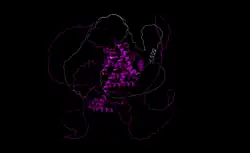

Progesterone receptor A

The progesterone receptor A (PR-A) is one of three known isoforms of the progesterone receptor (PR), the main biological target of the endogenous progestogen sex hormone progesterone.[1][2] The other isoforms of the PR include the PR-B and PR-C.[1][2]

PR-A is 164 residues shorter than PR-B in humans[3] and anywhere from 128-165 residues shorter in other organisms.[4] Each isoform binds its natural ligand, progesterone, but also demonstrates the ability to bind a number of other agonists including norethindrone, a synthetic progestin.[5]